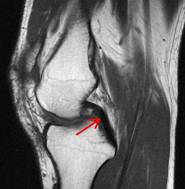

In order to help outline which structures are damaged further imaging in the way of magnetic resonance imaging (MRI) is often required. This is a very safe way of gaining detailed information about the knee and takes about 20 minutes in a scanner. There are high quality MR scanners at the Chelmsford Medical Centre, the Capio Springfield Hospital and Broomfield Hospital.